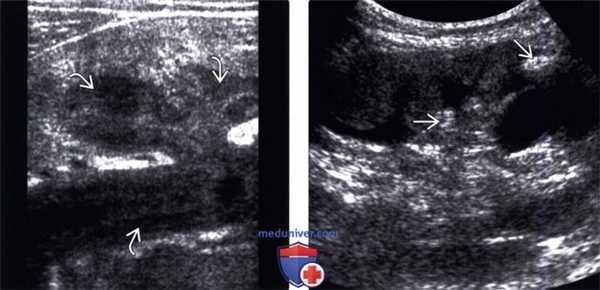

(Левый) На продольном ультразвуковом срезе высокого разрешения визуализируется выраженное утолщение слизистой в чашечно-лоханочной системе у пациента с фульминантным ТБС почки. Может имитировать пионефроз или новообразование.

(Правый) На продольном трансабдоминальном ультразвуковом срезе визуализируется ТБС почки с поражением сосочков. Папиллярный некроз визуализируется в виде окруженных жидкостью гиперэхогенных очагов без акустического затенения в мозговом веществе.